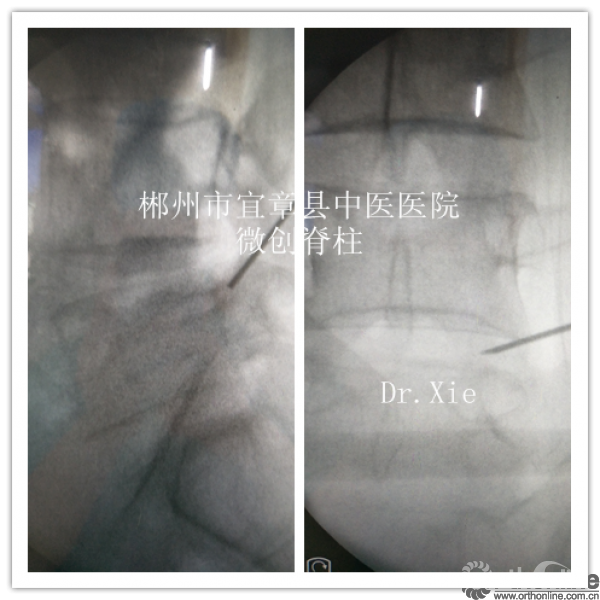

置管及成型时候正侧位情况